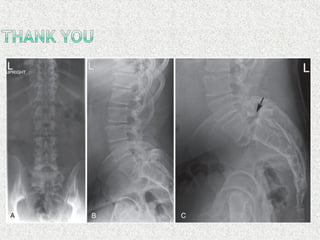

 LS spine X-ray

 AP

 Lat

 Lat flexion/extension

 LS spineX-ray  AP  Lat  Lat flexion/extension  Oblique if suspecting spondylolysis  MRI  SPECT  HRCT